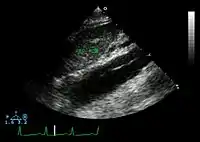

Ultrasound

The transesophageal echocardiogram (TEE) is a good test in the diagnosis of aortic dissection, with a sensitivity up to 98% and a specificity up to 97%. It has become the preferred imaging modality for suspected aortic dissection. It is a relatively noninvasive test, requiring the individual to swallow the echocardiography probe. It is especially good in the evaluation of AI in the setting of ascending aortic dissection and to determine whether the ostia (origins) of the coronary arteries are involved. While many institutions give sedation during transesophageal echocardiography for added patient comfort, it can be performed in cooperative individuals without the use of sedation. Disadvantages of TEE include the inability to visualize the distal ascending aorta (the beginning of the aortic arch), and the descending abdominal aorta that lies below the stomach. A TEE may be technically difficult to perform in individuals with esophageal strictures or varices.